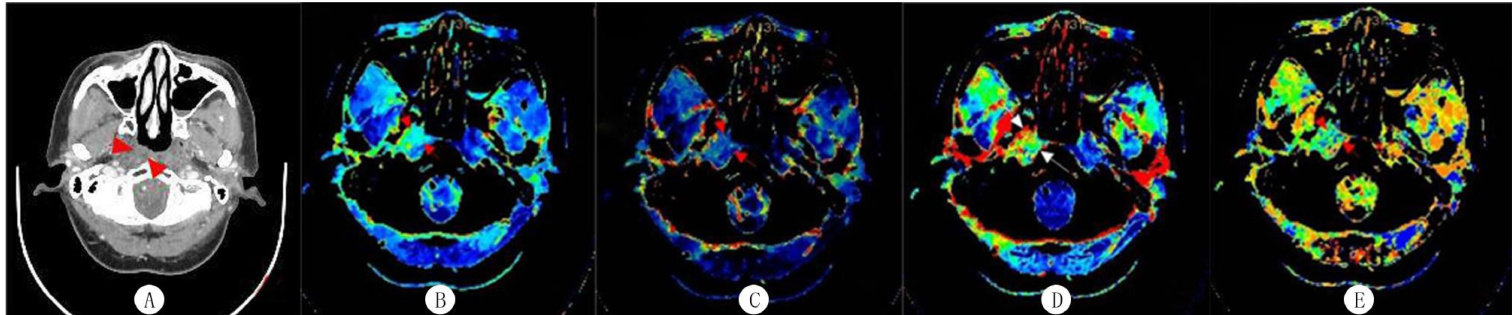

CT灌注成像对鼻咽癌放疗联合化疗效果的预测价值

[关键词] 鼻咽癌;化放疗;体层摄影术,X线计算机;灌注成像;治疗结果;预测[中图分类号]R739.63;R817.4 [文献标志码]A [文章编号] 2096-5532(2025)05-0705-05doi:10.11712/jms.2096-5532.2025.61.160 [开放科学(资源服务(剩余11031字)